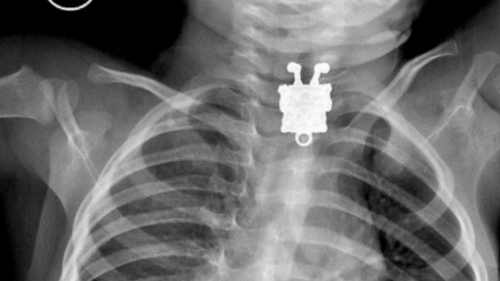

X光片顯示出一個(gè)“海綿寶寶”。

中新網(wǎng)1月29日電 據(jù)外媒報(bào)道,沙特一名醫(yī)生近日在為一名孩子拍攝X光片時(shí),驚訝地發(fā)現(xiàn)孩子體內(nèi)有一個(gè)“海綿寶寶”飾品。

據(jù)報(bào)道,這名醫(yī)生叫安吉利,他是阿卜杜拉阿齊茲國王大學(xué)醫(yī)院的放射科醫(yī)生。他告訴媒體稱,在X光片里能清晰看到孩子吞下的“海綿寶寶”卡通形象。

安吉利醫(yī)生說,從X光片里看,這個(gè)“海綿寶寶”像是一個(gè)吊墜,上面有可以掛繩子的地方。

“我覺得也可能是個(gè)別針,”安吉利醫(yī)生說,當(dāng)他第一次看到X光片的時(shí)候嚇壞了,一個(gè)“海綿寶寶”笑臉相迎的樣子讓他相當(dāng)震驚,“而且拍攝角度和朝向?qū)嵲谑呛芡昝馈?rdquo;